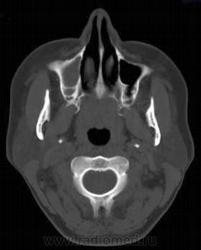

1. Эктопия зуба?

2. Хронический гайморит?